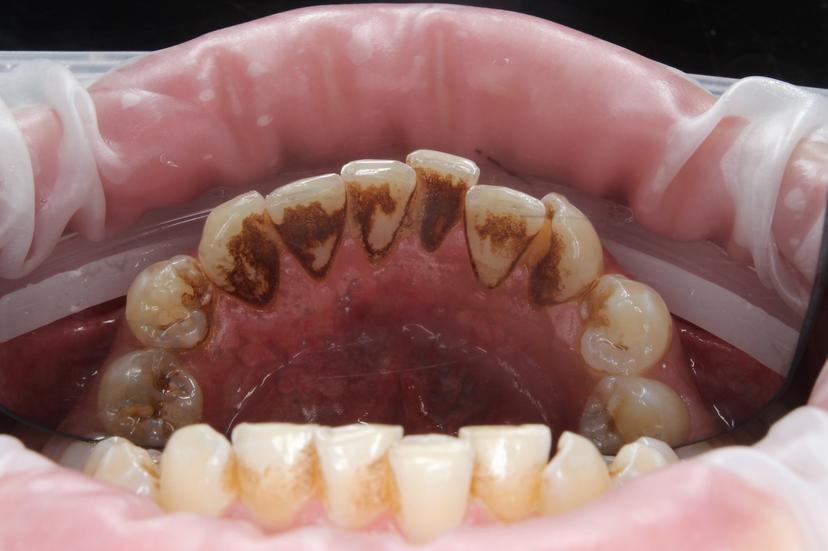

Пациент обратился с жалобами на зубные отложения: пигментированный зубной налет, мягкий зубной налет, наддесневой и поддесневой минерализованный зубной камень.

Удаление наддесневыз зубных отложений: пигментированный зубной надет, минерализованный зубной камень.

Пациент обратился с жалобами на зубные отложения: пигментированный зубной налет, мягкий зубной налет. Наддесневой и поддесневой минерализованный зубной камень.

Пациент обратился с жалобами на наросты на зубах: мягкий зубной налет, наддесневой и поддесневой минерализованный зубной камень.